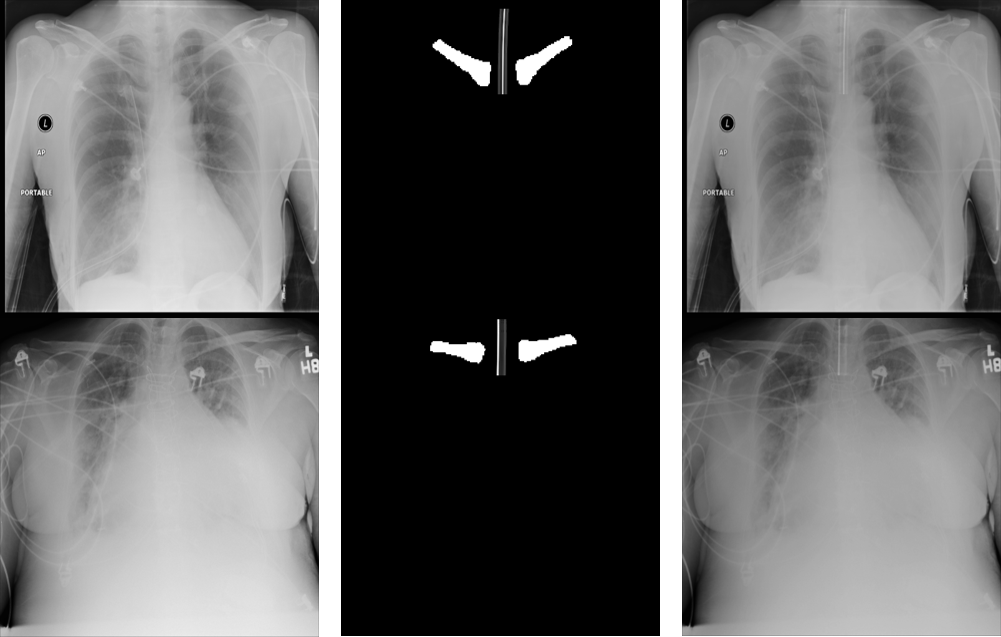

Refer to caption

Figure 6: Cases correctly classified with ET tube and their corresponding segmentation as overlay (in green color)

Training the combined model for classification and segmentation of ET tubes on synthetic X-ray images, we reached an AUC of 0.962 in classification accuracy. Using fine-tuning on real X-ray images, the accuracy improved to an AUC of 0.987 with both sensitivity and specificity over 95% (Figure 6). Figure 6 shows real chest radiographs from the test set that were classified correctly for presence of ET tube and their output segmentation maps.